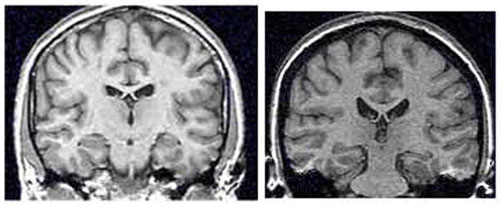

Poppa and her colleagues observed reduced connectivity in a brain network related to attention in women with PTSD compared to those without PTSD. In particular, women with PTSD displayed reduced functional connectivity between the orbitofrontal cortex and the precuneus, mid-posterior insula, lateral prefrontal cortex, and angular gyrus.

Regardless of PTSD diagnoses, exposure to sexual violence was independently associated with similar reductions in connectivity in this brain network as well.

“These findings add to a body of evidence that trauma lastingly changes how our brains function. Also, given the high co-occurrence of trauma and substance abuse disorders, understanding these brain changes may have a role in improving treatment outcomes,” Poppa told PsyPost.